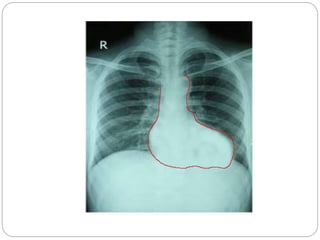

Chest X-Ray

 Plain films may classically show a "boot shaped"

heart with an upturned cardiac apex due to right

ventricular hypertrophy and concave

pulmonary arterial segment